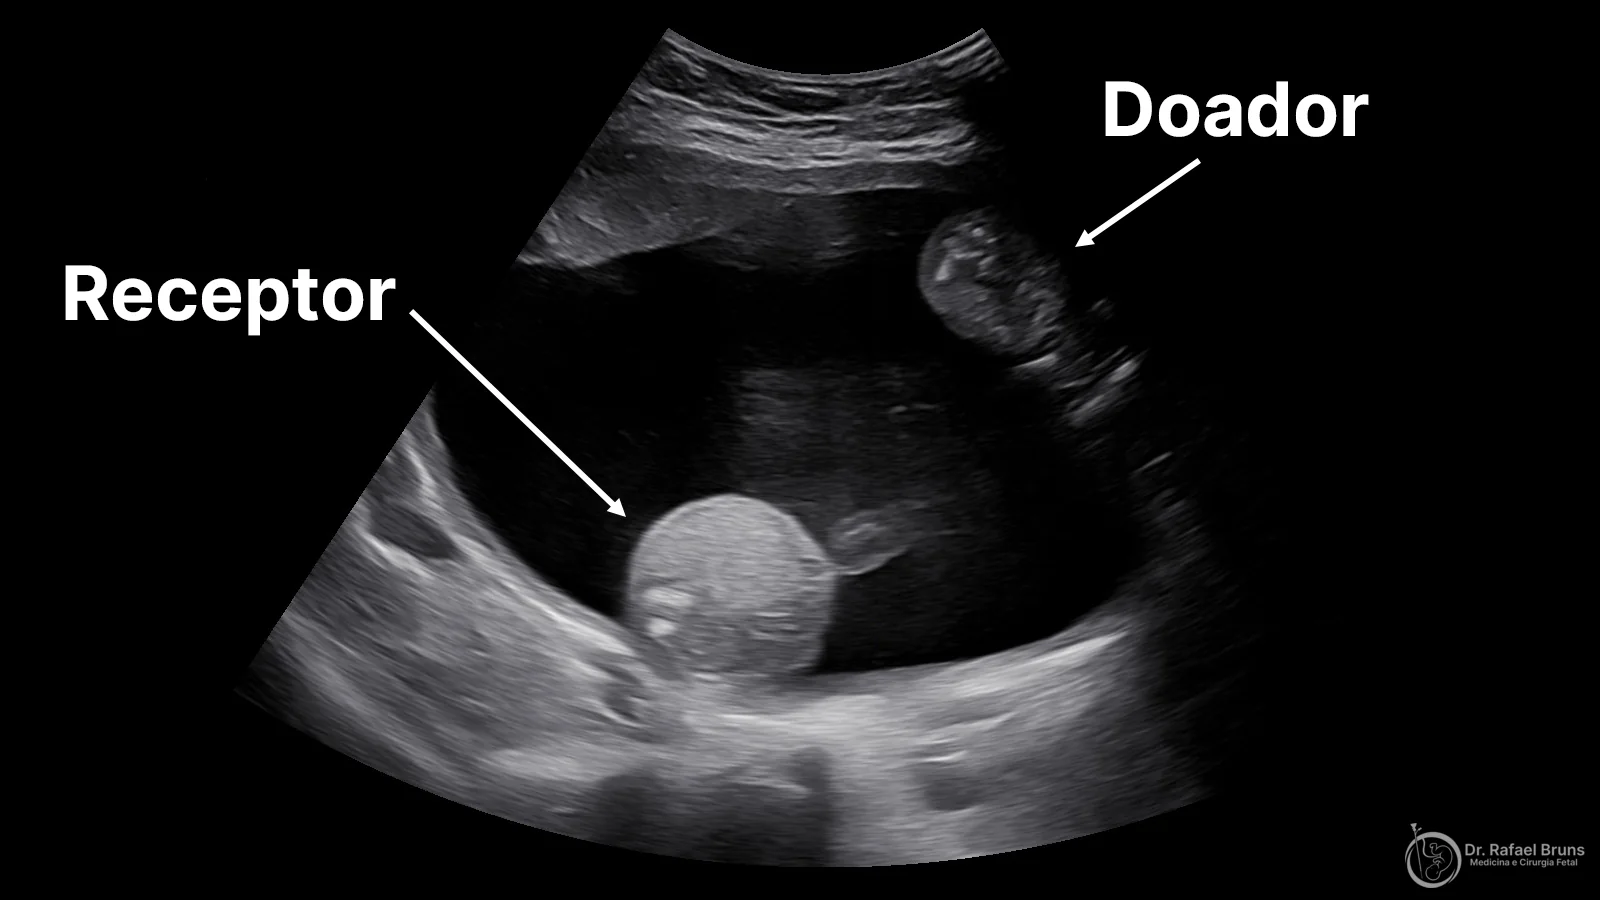

Ultrassonografia de síndrome de transfusão feto-fetal mostrando feto receptor com polidrâmnio e feto doador comprimido como stuck twin na parede anterior

Ultrassonografia de um caso de STFF: o feto receptor (abaixo) apresenta polidrâmnio com grande volume de líquido amniótico. O feto doador (menor, acima) está comprimido contra a parede uterina anterior como stuck twin — preso pela membrana intergemelar na ausência de líquido ao seu redor. Imagem do acervo pessoal do Dr. Rafael Bruns.